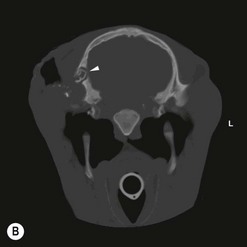

image image image

Fig. 13.43 Radiograph (A) and CT images (B and C) of a compound odontoma in a 2-year-old TB colt.

(Images courtesy of J. Easley.)